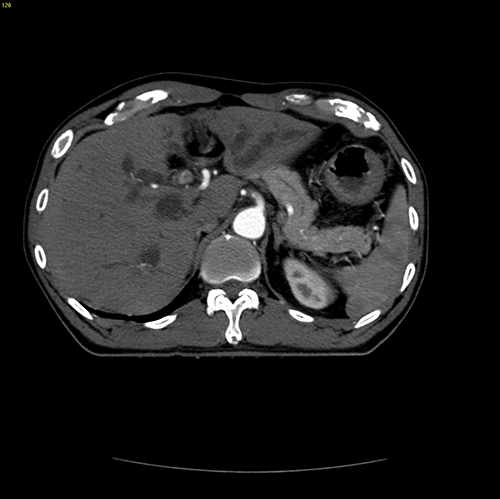

IV型胆管癌---胆管癌根治(左半肝+尾状叶切除)